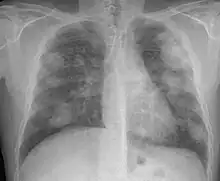

La silicosis complicada se caracteriza por la existencia de masas de Fibrosis Masiva Progresiva, también llamadas masa conglomeradas, con diámetro mayor de 1 cm. Es una enfermedad grave, sobre todo si las masas son de gran tamaño, y disminuye notablemente la esperanza de vida de los pacientes. La evolución de la forma simple a complicada se debe a factores muchas veces desconocidos. Entre los factores conocidos destacan: elevada exposición a sílice, abundante profusión nodular, tuberculosis y enfermedades del colágeno.

La OIT clasifica las masas de FMP) según su diámetro mayor como A (exceden 10 mm), B (aisladamente o sumadas exceden 5 cm) y C (exceden un área equivalente a la de lóbulo superior derecho.

En caso de dudas diagnósticas se puede recurrir a la Tomografía Computada de Alta Resolución (TACAR) que se ha mostrado más sensible y específica para el diagnóstico.[9] Somete al paciente a mucha más radiación que la Rx y no debe usarse como prueba diagnóstica de primer nivel sino para aclarar dudas. La TACAR permite comprobar cómo las masas de FMP se originan frecuentemente en región subpleural de zonas apicales posteriores desplazándose progresivamente de la pleura —signo del desprendimiento—.[3]